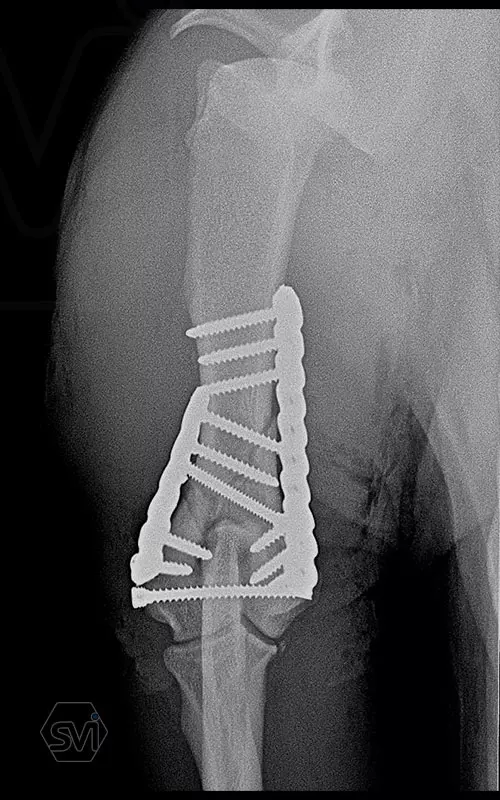

Yesterday, we operated on a Y fracture of the humerus of a 9-month-old French bulldog dog, where we used a cutable mini polyaxial straight plate (material thickness 2.0mm) and 2.4 polyaxial screws.

The fracture was favorable, the bone was not too fragmented, so we were able to plate the medial side easily, then turning the dog over, we replaced the lateral fragment as well and fixed it with a 2.4 intercondylar lag screw and with a shorter stright plate . It was very easy to work with the new plate, the surgery time was less than 2 hours. The stability is there, we placed a blind plug (screw head) in the lateral empty holes so that there is no weak point on the plate. The plate has mini polyax holes in which 2.4 and 2.0 polyax screws can be inserted (mini, 2.0-2.4 polyax system).

This plate arrangement and size is excellent for the treatment of the so common French bulldog humeral Y fractures.